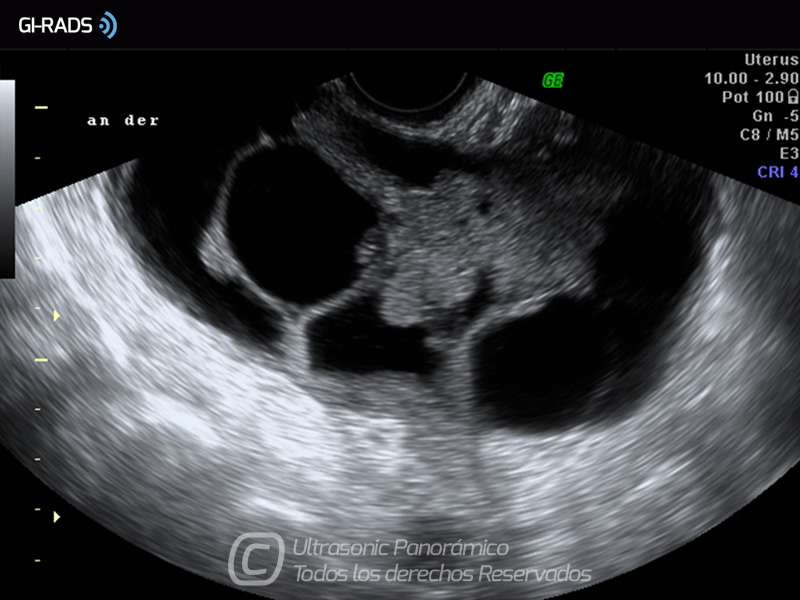

Cáncer Anexial – Áreas Sólidas

• Cáncer Anexial – Áreas Sólidas